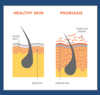

What do these photos show?

Psoriasis

- affects around 3% of the population

- can look similar to eczema

- immune related condition

Presentation:

- plaque (rasied) lesions

- salmon-pink

- silvery scale?

- well-defined lesions

What causes psoriasis?

Genetic susceptibility and an environmental trigger

- then the immune process occurs

- T-cells predominate in the dermis

- stimulates cytokine release (TNF-alpha)

- leads to neutrophils going into epidermis

- overproduction of keratinocytes

- thickening of the epidermis

- top-layer is immature and haven’t lost their nuclei, causing the scaling

Outline the histology of psoriasis

Hyperkeratosis

- thickening of stratum corneum

- scaling of stratum corneum

Parakeratosis

- retention of nuclei in stratum corneum

Acanthosis

- thickening of epidermis

Inflammation

- blackish, inflammatory cells

Dilated blood vessels